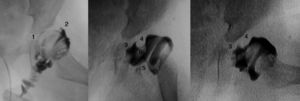

Cuanto mayor es el niño, mayor es la dificultad para conseguir la reducción, por lo que la eficacia del arnés de Pavlik disminuye. La artrografía valora de forma precisa la calidad de la reducción ya que permite visualizar las partes blandas de la articulación y la forma y el tamaño de la parte cartilaginosa del acetábulo y la cabeza femoral53 (fig. 4). La reducción ha de ser concéntrica y estable en una posición funcional. Si en la artrografía no se observa una reducción anatómica, se debe proceder a realizar una reducción abierta liberando los obstáculos intra-articulares y extra-articulares que impidan la reducción: el pulvinar, el labrum, el ligamento teres hipertrófico, el ligamento transverso, el tendón del psoas y la capsula anteromedial3. Las estructuras interpuestas, en el caso de intentar una reducción cerrada en presencia obstáculos, incrementarán la presión sobre la cabeza femoral, incrementando el riesgo de oclusión de los canales cartilaginosos o del drenaje venoso y provocando una necrosis avascular de la cabeza femoral. Es muy importante recordar que el tratamiento con una reducción cerrada en presencia de estructuras interpuestas lleva a un mal resultado a largo plazo e incrementa el riesgo de necrosis avascular53. Por lo tanto, es imperativo realizar una artrografía en aquellas caderas luxadas o subluxadas para valorar la necesidad de una reducción cerrada o abierta.

Artrografía de una cadera. En el caso A puede verse una reducción correcta de la cadera sin acúmulo medial de contraste (1) y con una espina de rosal (2), que se corresponde con el contraste existente entre la cápsula y el labrum. La artrografía del caso B muestra un acúmulo medial de contraste (3), que indica la reducción incorrecta de la cadera, existiendo obstáculos para la reducción: el labrum (4), el tendón del psoas (5) y el ligamento redondo (6). En el caso B esta contraindicado realiar una reducción cerrada de la cadera, siendo necesario realizar una reducción abierta para eliminar los obstáculos anatómicos.